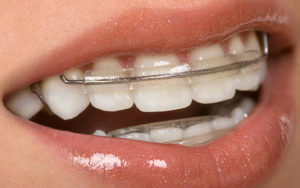

Пластинки для зубов для красивой улыбки

Большой процесс дефектов прикуса требует зависит от состояния полости рта и вредных привычек.